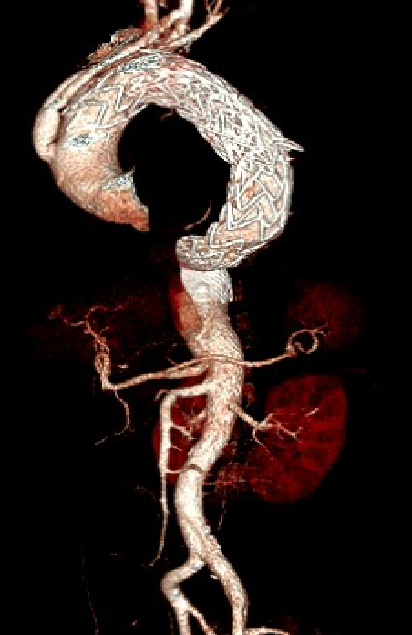

男,52岁,慢性夹层。2015年8月入院,4年前曾因B型层行TEVAR术,主动脉解剖变异,扭曲。行双烟囱+TEVAR术。术后第3天RTAD ,死亡。